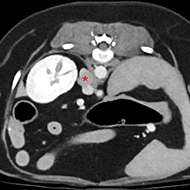

Research from the Royal Veterinary College (RVC) has found that epicardial pacemakers (EPs) can result in positive outcomes for cats suffering from severe heart conditions.

Findings revealed that EP implantation supported artificial cardiac pacing (ACP), which was effective in resolving symptoms such as abnormally slow heart rates (bradyarrhythmia).

The primary reasons that cats were referred for treatment included bradycardia and collapsing episodes. A third-degree atrioventricular block was found to be the most common indicator of pacemaker placement.

Image © RVC